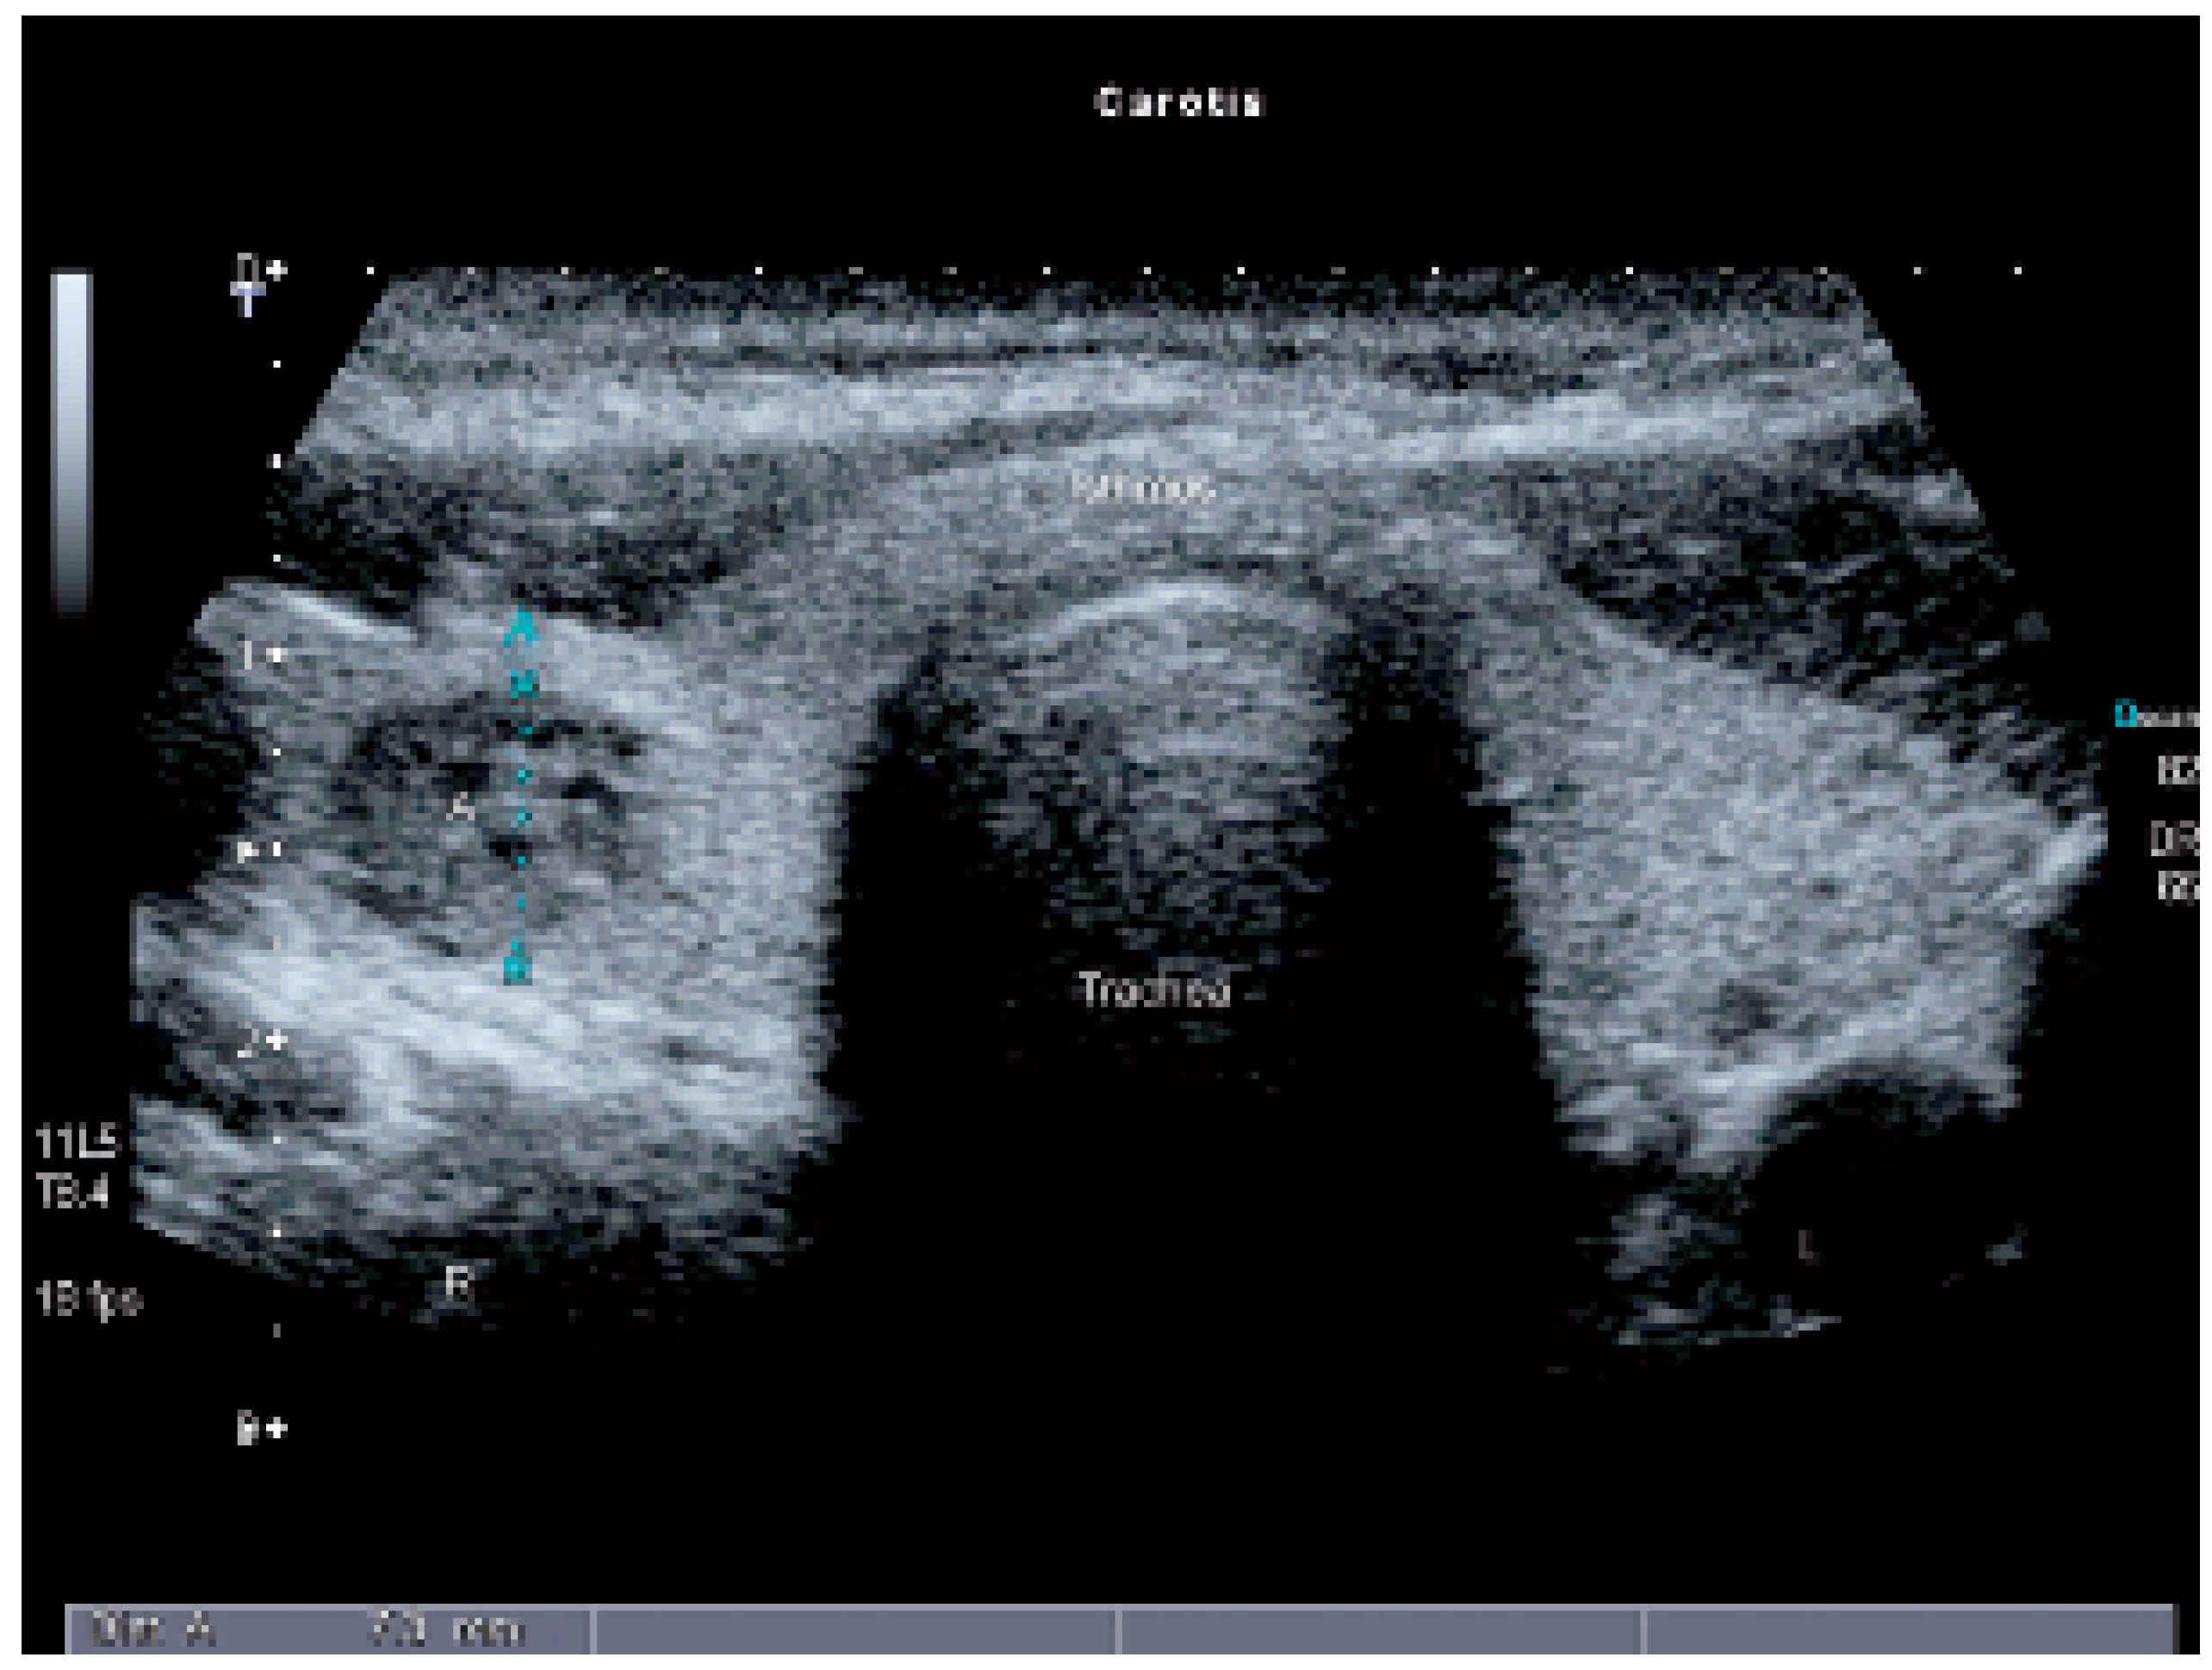

Autonomes Schilddrüsenadenom und Angiosonographie